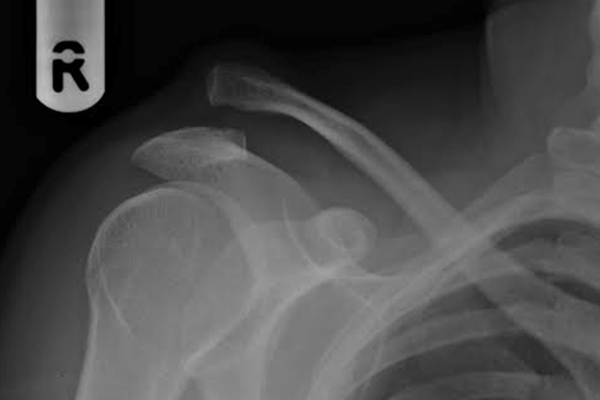

A-C JOINT DISLOCATION